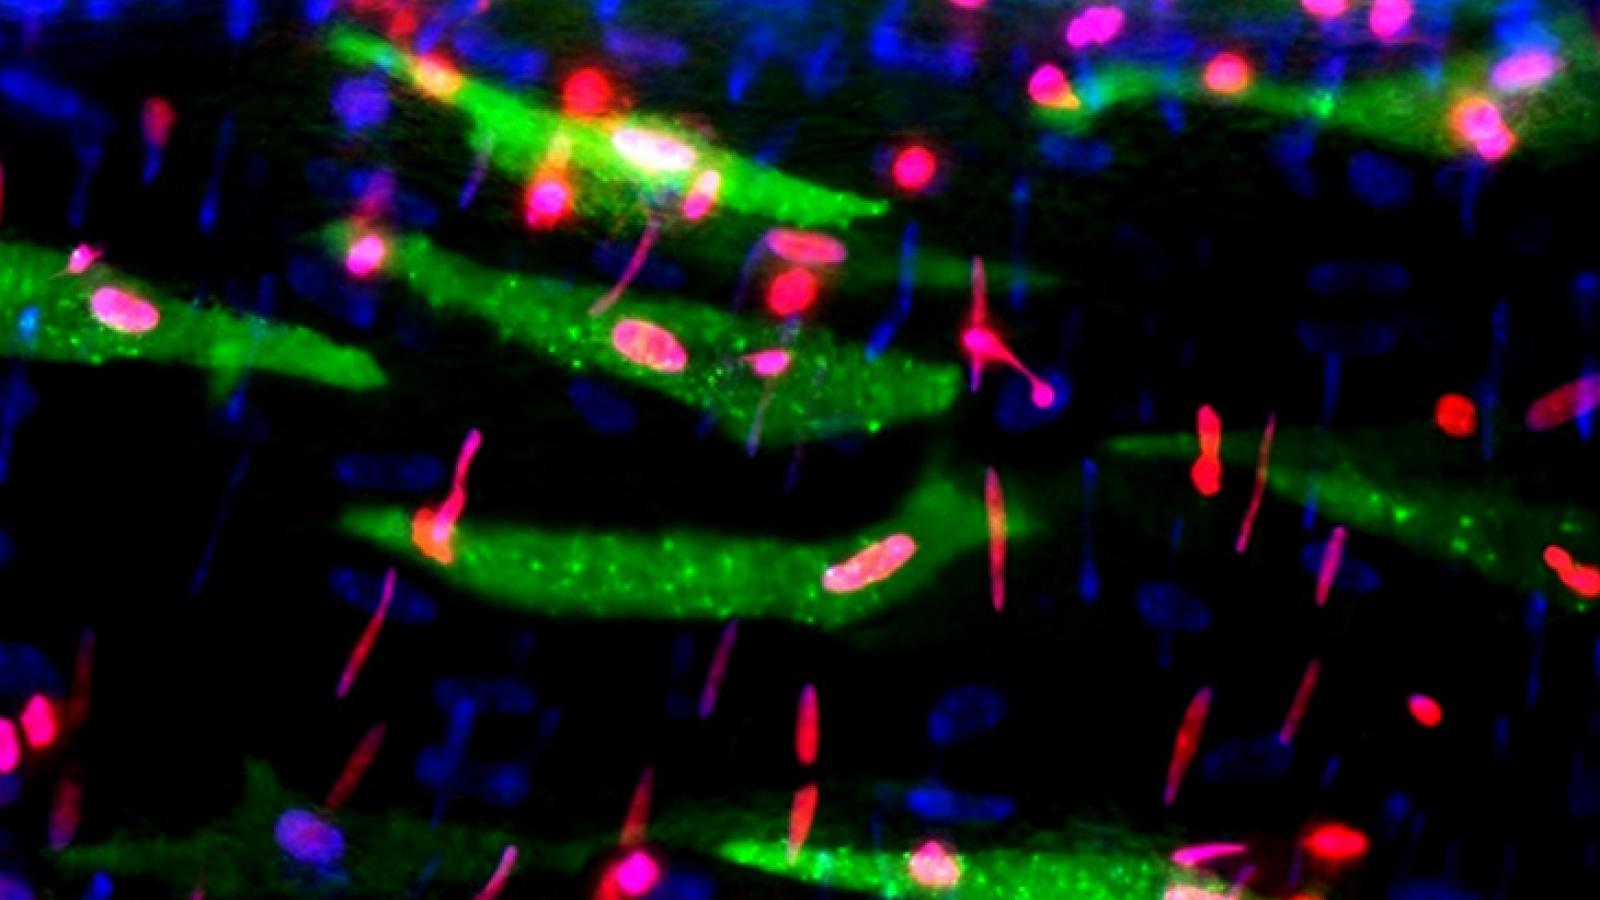

Pre-clinical research studies investigate a wide range of diseases, including infectious disease, cancer, immunology, cardiovascular disease, metabolic disorders, kidney disease, liver disease, digestive disorders, neuromuscular disease, sleep apnea and eye disorders. The controlled environment of the vivarium allows the therapeutic effects of exercise, nutrition, and novel therapeutics to be examined in unique rodent models. The vivarium is managed by the Animal Care Quality Assurance office in conjunction with the School of Medicine Scientific Directors for the Vivarium.